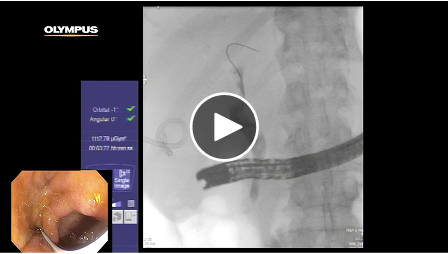

Removal of Distal Common Bile Duct Stone

Dr. Cavanagh performs diminutive papilla cannulation and distal CBD stone removal in a patient who presented with RUQ abdominal pain.